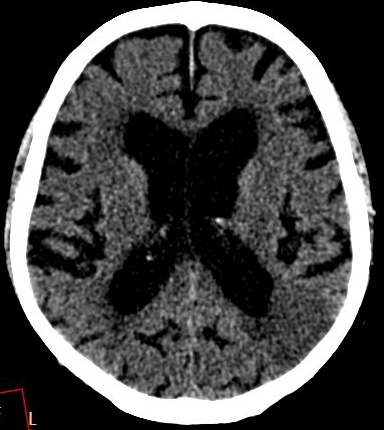

Infarcts of microangiopathic origin can be lacunar infarcts that develop due to the complete or the partial occlusion of the cerebral arterioles. They predominantly occur at the basal ganglia, thalamus, internal capsule and the pons.

Biswanger’s disease (subcortical arteriosclerotic encephalopathy) is also results from microangiopathy.

In acute phase (12-24 hours after the occlusion of the middle cerebral artery) on CT hypodense basal ganglia, the loss of cortical white-grey matter differentiation and sulcal effacement are the characteristic imaging findings.

In the chronic phase of the infarct (months to years) the hypodensity of the lesion (CT) reaches the level of the cerebrospinal fluid. There is no more contrast enhancement, the lesion is well differentiated and it degenerates into a cyst secondary to encephalomalacia. The brain parenchyma experiences a volume decrease due to the degeneration (sometimes calcifications can occur at the marginal border of the infarct).